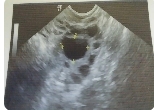

在受精卵成功著床后約5-6周時,會出現(xiàn)孕囊的跡象。此時,在B超檢查中可以看到一個小小的液體囊泡,并且可以聽到心跳聲。如果您沒有出現(xiàn)任何流血或其他健康問題,則可以在4到7周內(nèi)進(jìn)行第一次B超檢查。

在第一次B超檢查中,醫(yī)生將使用陰道探頭進(jìn)行內(nèi)部掃描來確定孕囊的大小和位置。孕囊通常會在子宮內(nèi)形成,并且可以清晰地看到其輪廓和形狀。同時醫(yī)生還會檢查是否有多個孕囊或其他健康問題。

在受精卵成功著床后約5-6周時,可以開始看到孕囊。如果您想確定胚胎是否已經(jīng)成功著床并形成孕囊,則需要通過B超檢查來確認(rèn)。在第一次B超檢查中,醫(yī)生將使用陰道探頭進(jìn)行內(nèi)部掃描來確定孕囊的大小和位置。